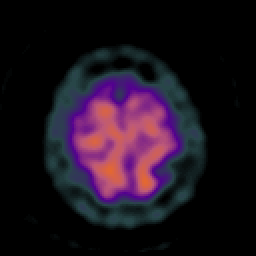

Huntington's Chorea, MR -- Slice #18

[Home][Help][Clinical] Slice 18